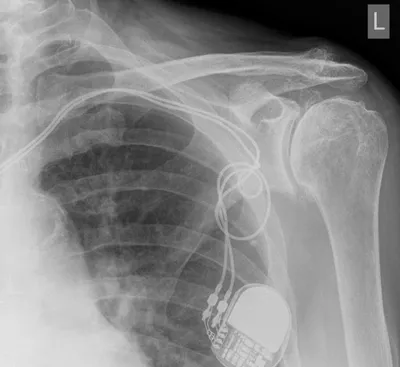

Pacemaker Radiology Images

This collection contains 1 radiology images related to pacemaker, including various imaging modalities such as X-rays, MRIs, CT scans, and ultrasound images commonly used in medical diagnosis and education.